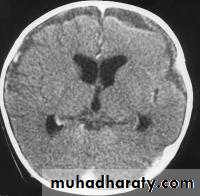

Bacterial Meningitis with cerebral oedema